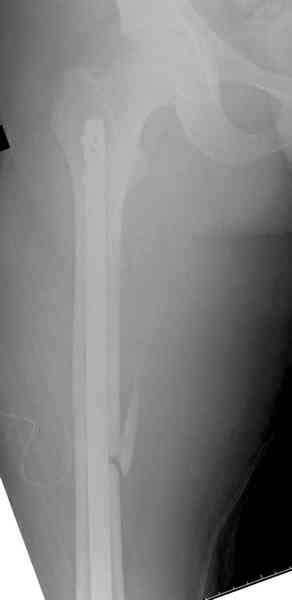

Пострадавшему 21 г., травма скоростная, после I&D с расширением раны, на бедре сделана операция ретроградным интрамедуллярным штифтом, остеосинтез с частичной резекцией надколенника и ушивание собственной связки.

На голень наружный фиксатор, рану на бедре ушили (рана была изнутри кнаружи всего 2 см). По протоколу травматических больных, до операции обследован ангиографически, (у больного дистально не смогли определить пульсацию) сосудистый хирург подтвердил проходимость на всем протяжении магистрального сосуда нижней конечности по снимкам ангиограмм.

В настоящее время больной в реанимации по поводу Черепно Мозговой Травмы и состояние улучшается. Запланировал ушивание раны в пятницу, если позволит состояние мягких тканей и при отсутстви отека возможно удастся просунуть перкутанномедиальную пластину.